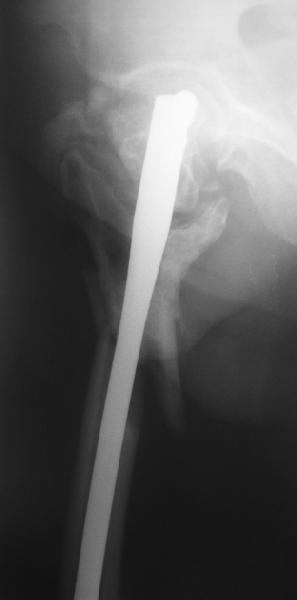

На прошлой неделе оперировали похожего пациента. 2 года после

неудачного остеосинтеза PFN в другом регионе. После удаления остатков

железа выявилось несращение вертельной области.

Поскольку в нашем случае выявилась подвижность, мы наложили дистрактор

таз-бедро на 3 дня, и сделали остеосинтез гаммой без остеотомии. То,

что произошла "корригирующая остеоклазия" в подвертельной области,

выявили после введения гвоздя. Пациент уже уехал домой, будем

наблюдать.